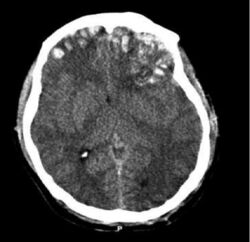

Computerized tomography (CT) scan showing brain multiple frontal, parietal, and temporal lobe lesions.[26] The cause of deep dyslexia is damage in the left hemisphere of the brain

Deep dyslexia is usually classified as an acquired reading disorder, as opposed to a developmental dyslexia, in previously literate adults as a consequence of a brain injury.[2][21][10][4] However, recently, developmental deep dyslexia has also been reported in children with Williams syndrome.[10][27]